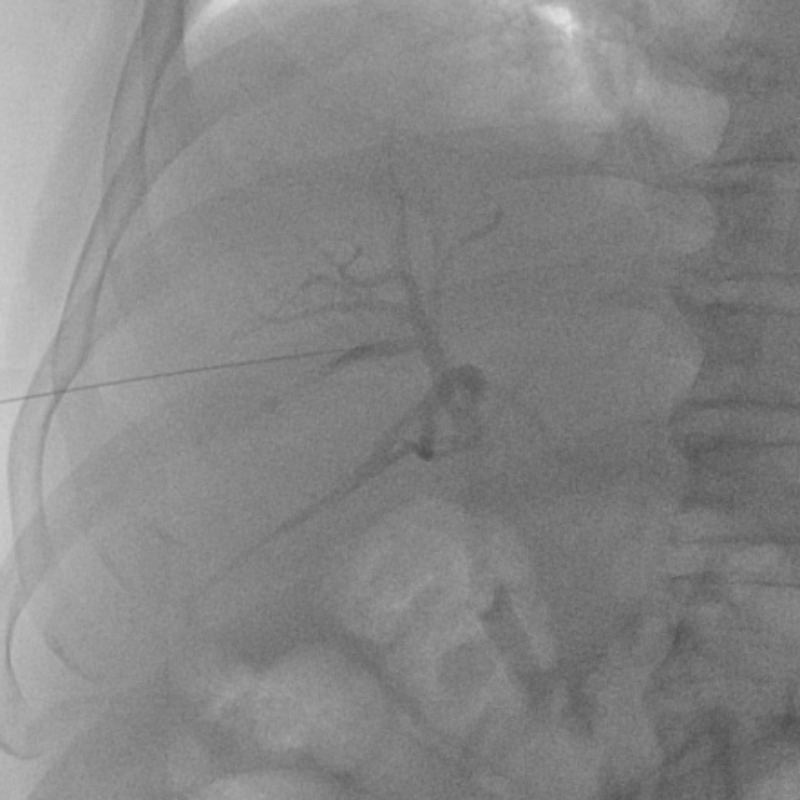

情況緊急,普通外科團隊第一時間進行術前病情討論,經過反復論證,普通外科團隊立即給予在插管全麻下行經皮經肝膽管穿刺置管引流術(PTCD)。

手術順利,膽道引流管引流通暢,未出現手術并發癥。手術結束后患者出現譫妄,拔除胃減壓管,拒絕留置胃管,普通外科團隊根據實際情況,給予了患者中藥清胰湯口服及灌腸治療。繼續予積極抗感染、制酸護胃、醋酸奧曲肽抑制胰酶分泌,護肝治療,胰島素降血糖治療,補液止痛等治療。在普通外科醫護人員的精心治療下,李大爺逐漸好轉,術后7天李大爺血尿淀粉酶及膽紅素正常。